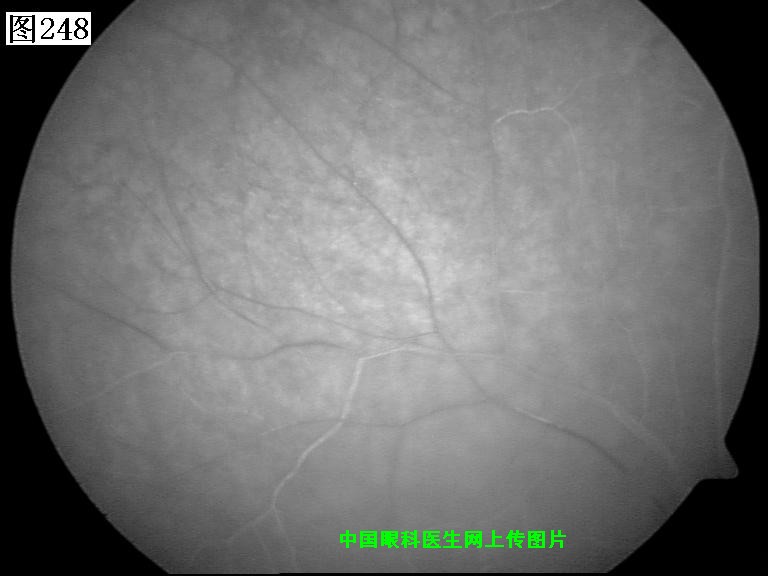

245 246 247 248